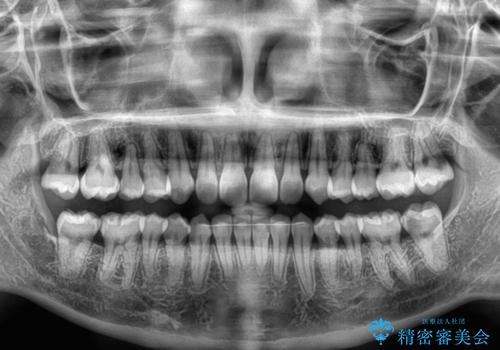

- 前歯のデコボコと歯肉に埋もれている奥歯を気にして来院された患者様です。

インビザラインでの治療を希望されていましたが、左右の下顎大臼歯が歯肉に埋もれており、特に右側は歯軸が顕著に傾斜していたため、インビザライン単独での治療は困難と判断し、ワイヤー装置を併用することとしました。

ワイヤー装置での下顎臼歯改善には時間がかかることが予想されたため、下顎のワイヤー矯正と並行して上顎をインビザラインで整え、その後インビザラインにより上下歯列を整える矯正治療を行うこととしました。

ワイヤー装置を併用したことで、レントゲン写真からも分かるとおり歯軸をしっかりと改善させることができました。